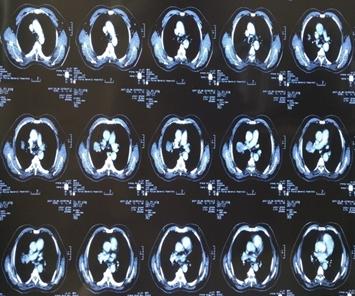

因二次全麻下气管插管出现哮喘无法手术,于2007年5月30至2007年6月28日进行局部放射治疗,同时给予对症支持治疗。照射剂量PTV(肿瘤外5mm)66GY/22f/30d;GTV(肿瘤边缘)70GY/22f/30d;GTV1(肿瘤内部)77GY/22f/30d;治疗期间,咳嗽缓解、无咯血,血常规 基本正常 范围,按计划完成治疗。

治疗后5年复查,患者偶有咳血,局部病灶纤维化改变